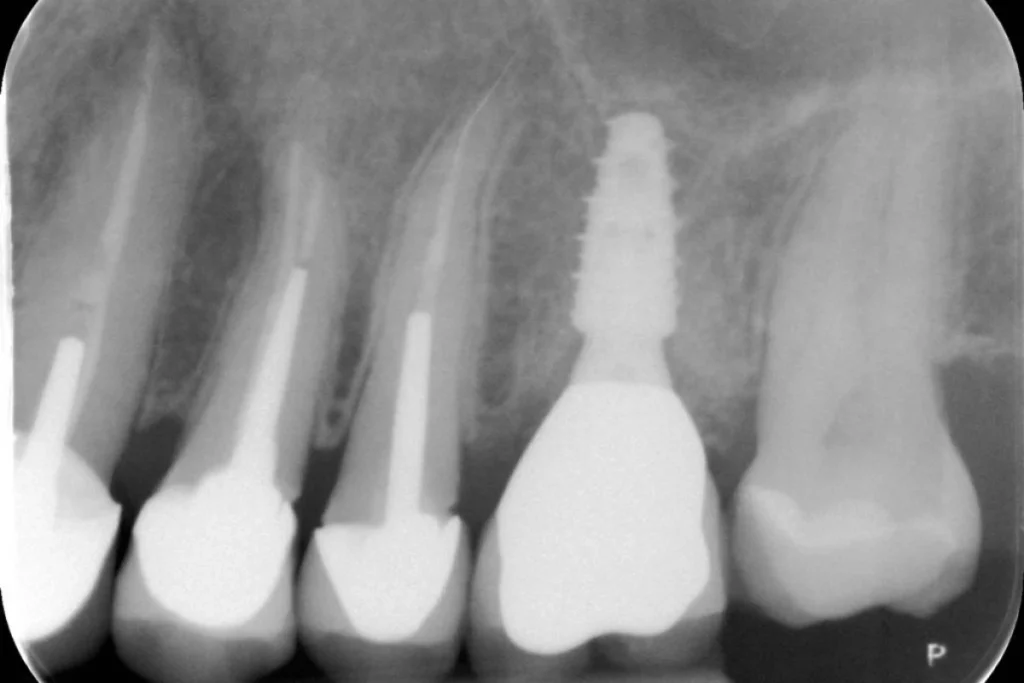

Cas clinique 3 – Mise en place d’un implant dentaire le jour de l’extraction

Nous vous présentons le cas de Mme B. 53 ans, qui consulte suite à des douleurs sur sa molaire supérieure gauche.

Après un examen clinique et radiographique, le verdict tombe… la dent n’est malheureusement plus conservable.

Après lui avoir exposé les différentes solutions, Madame B. souhaite remplacer sa dent par un implant. C’est la solution de choix pour retrouver une dent fixe sans avoir à abimer les dents de part et d’autre. L’analyse du scanner nous permet de proposer à Madame B. une extraction implantation immédiate. Il s’agit de réaliser en une seule et même séance l’extraction de la dent condamnée et la mise en place de l’implant dentaire.

Cela permet d’éviter une 2ème chirurgie à notre patiente et de raccourcir la durée du traitement de plusieurs mois. Un comblement osseux est réalisé le jour de l’intervention.

3 mois après la pose de l’implant, la patiente peut retrouver une dent fonctionnelle et esthétique.